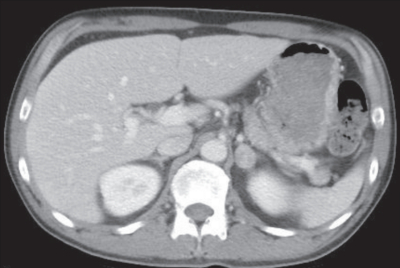

検査所見:尿所見:蛋白(-)、糖(-)、潜血(-)。血液所見:赤血球 437 万、Hb 12.3 g/dL、Ht 34 %、白血球 5,400(好中球 45 %、好酸球 21 %、好塩基球 1 %、単球 9 %、リンパ球 24 %)、血小板 23 万。血液生化学所見:総蛋白 6.3 g/dL、アルブミン 3.7 g/dL、 総ビリルビン 0.5 mg/dL、 直接ビリルビン 0.2 mg/dL、AST 43 U/L、ALT 78 U/L、LD 169 U/L(基準 120~245)、ALP 200 U/L(基準 38~113)、γ-GT 96 U/L(基準 8 ~50)、CK 100 U/L(基準 30~140)、 尿素窒素 11 mg/dL、 クレアチニン 1.0 mg/dL、 尿酸 3.7 mg/dL、 血糖 92 mg/dL、Na 118 mEq/L、K 4.6 mEq/L、Cl 89 mEq/L、Ca 8.4 mg/dL。 血清 浸透圧240 mOsm/L(基準 275~288)、 尿浸透圧 572 mOsm/L(基準 50~1,300)、 尿中Na 84 mEq/L。 胸部エックス線写真と胸腹部造影 CTを別に示す。